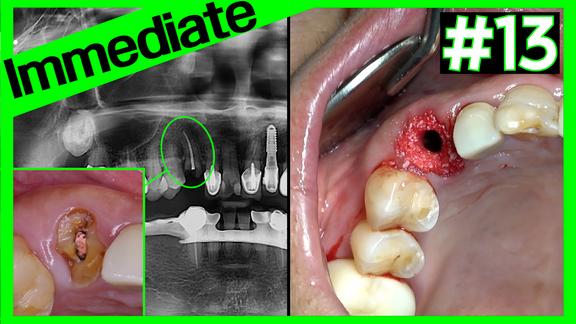

#46i Immediate & A-Oss Collagen

Online Surgery